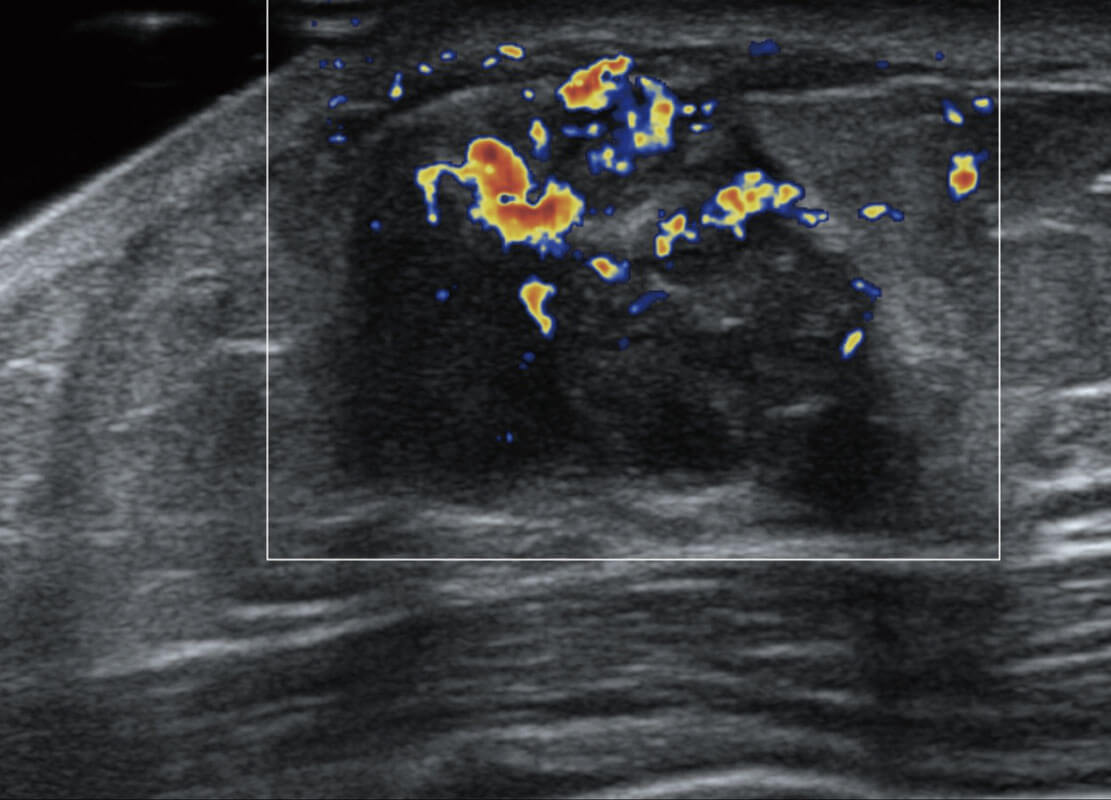

P60搭载宽频带线阵探头、宽景成像、弹性成像技术,为您提供乳腺应用方案。P60支持高频相控阵探头、线阵探头、腹部高频探头、腹部微凸探头等,丰富的探头群搭载敏感的彩色血流成像,适用于新生儿多种脏器检测要求,满足新生儿筛查需求。

乳腺导管癌

乳腺癌显微血流